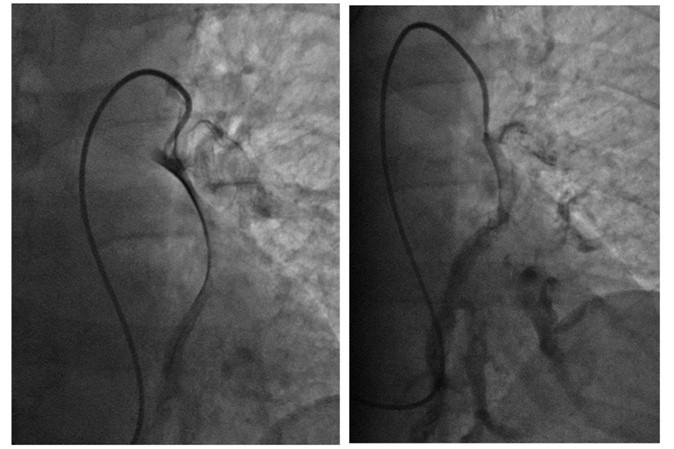

В больнице рассказывают, что одним из первых пациентов, на котором опробовали метод механической фрагментации тромба, стала 18-летняя девушка. В тот день утром ее выписали из другого стационара после операции на сломанном бедре, а вечером ее доставили в сосудистый центр больницы № 20 в тяжелом состоянии с симптомами тромбоэмболии. Врач-реаниматолог Владимир Радионов предложил попробовать разрушить тромб, который то перекрывал ток крови полностью, то частично открывал артерию. Для этого в легочную артерию под рентген-контролем ввели катетер, который обычно используется для оценки гемодинамики в отделах сердца. Девушка открыла глаза и стабилизировалась прямо на операционном столе и в скором времени была выписана из стационара со значительным улучшением.

Применяемая в 20-й больнице методика позволяет врачам через один прокол проникнуть в венозную сеть, откуда через сердце добраться до легочной артерии и ее ветви. Тромб разрушается на фрагменты. Это позволяет быстрее его растворить и избежать тяжелых осложнений за счет сокращения времени и снижения количества препарата. Врач наблюдает за процессом с помощью ангиографа. Для этого пациенту в кровь вводят контрастное вещество.